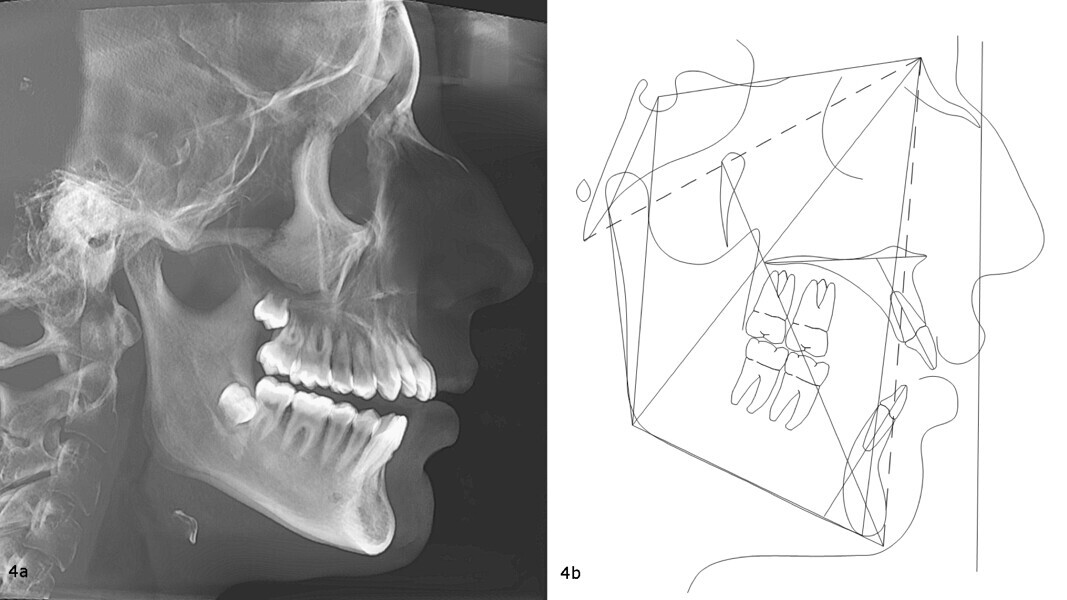

The panoramic radiograph confirmed the presence of all four third molar germs. Notably, there was advanced root resorption in the maxillary arch, although the overall periodontal health appeared good (Fig. 3). The cephalometric analysis showed a Class II skeletal pattern, a vertical growth tendency and posterior mandibular rotation. The maxillary and mandibular incisors were found to be slightly proclined (Fig. 4).

Beyond the occlusal and aesthetic improvements, vertical control had delivered significant facial changes, including a shortening of the lower facial third, improved upper and lower lip support, and an advancement of the chin by 5 mm (Fig. 13). Importantly, all of these changes were achieved without exacerbating the initial root resorption, as confirmed by the final panoramic radiograph (Fig. 14). The final cephalometric radiograph and tracing confirmed the successful treatment outcome, showing clear evidence of mandibular auto-rotation and a shortened lower facial third, contributing to improved facial proportions (Fig. 15).